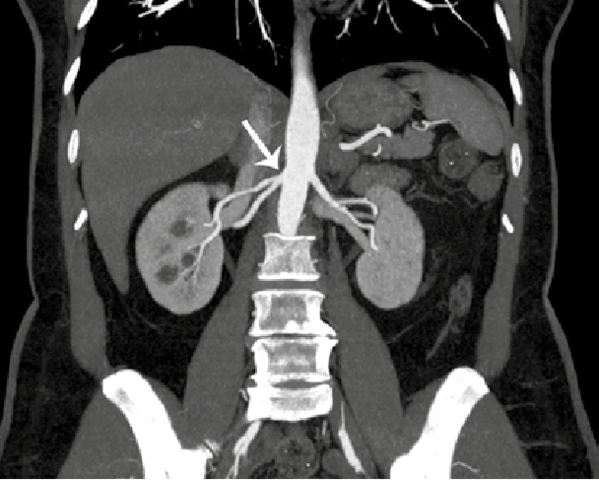

• 2002 - Uso de Yodo

2002 - Uso de Yodo

Se utiliza yodo como medio de contraste para visualización de tejidos y riesgo vascular